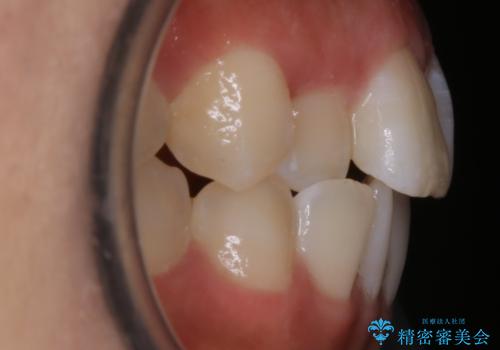

【非抜歯】部分矯正でも治る 前歯の反対咬合

- 前歯にガタつきを主訴にご来院されました。

奥歯の嚙み合わせに問題がほとんどみられなかったため、インビザライン ライトパッケージでの部分矯正を行うこととなりました。

今回のケースでは奥歯の噛み合わせに問題がほぼみられなかったため、前歯の位置のみに焦点を当て部分矯正を行いました。